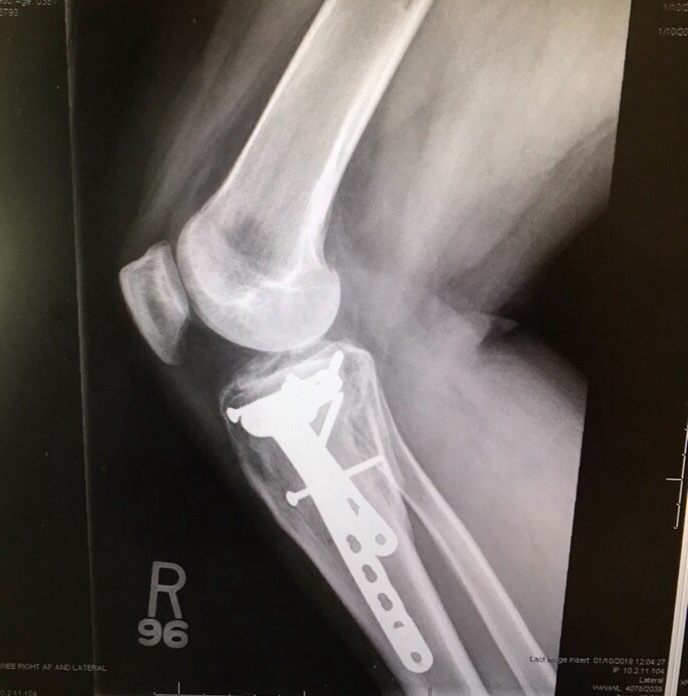

The second surgery repaired my ligaments with cadaver, and “installed” enough metal screws, rods and plates for me to be “bionic Jules” and set off airport alarms.  The pain coming out of surgery was like, well, I’ll be redundant.  It was a special kind of hell. I hallucinated with pain in the days and nights after, and poor Nicholas was alone with me on one of my worst nights.  I was convinced that I was Wonder Woman and I was going to fly off the table, fueled with pain….it was truly awful, and I didn’t have to be the one to watch helplessly.

When Zelda (my mint-green moped) and I disagreed last summer and I shattered my knee, PDS was the first to send some love to the Trama Unit; and the love and support didn’t stop there.  We had the best of restaurant and home cooked Indian food delivered to our door, flowers in pink ball jars, thoughtful “couch-bound” care packages, and constant message of encouragement and offers to help. I ugly snot-cried at Nicholas’ going away party, and fully expected the work bonds in Atlanta to be a lucky anomaly that we would be hard pressed to ever find again.